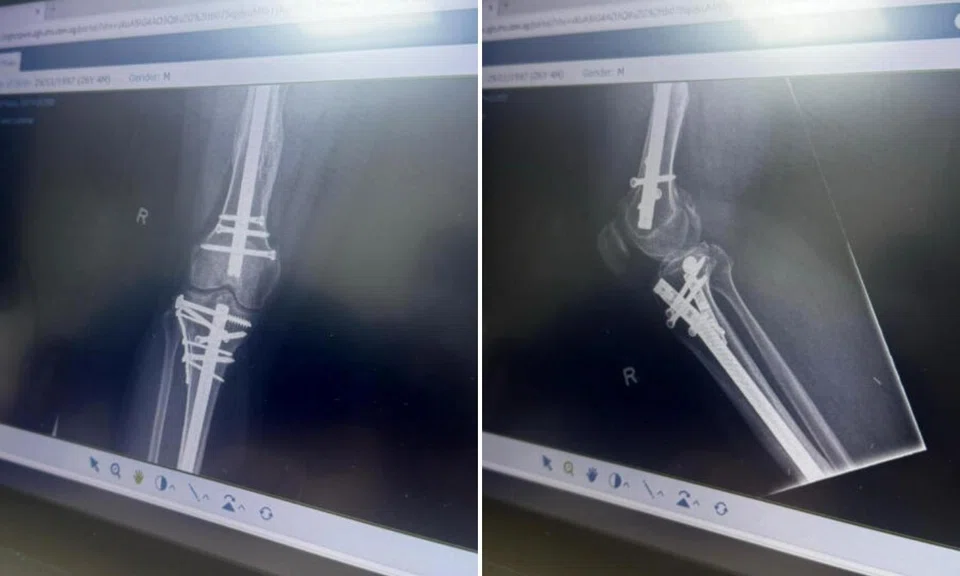

Mr Mahmud, who was crushed between two cars, suffered a traumatic brain injury, damage to his spinal cord, and multiple fractures on his right leg. There was also a hole on his chin caused by flying debris.

He now has a metal rod in his right leg and multiple screws in his neck and shoulders.